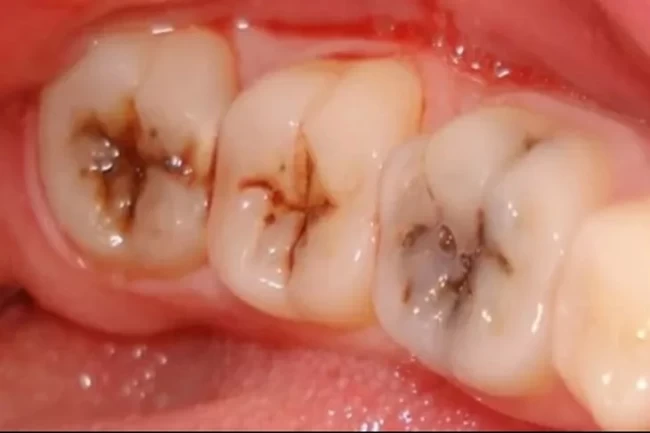

Kolanın en çok dişlere zarar verdiğinin de altını çizen uzmanlar, "Kola ve diğer asidik içecekler, diş minesine zarar vererek çürümelere yol açar. Ayrıca Gençler arasında daha çok tüketilen kolanın geç yaşta diş ömrünü azaltır." diyor.